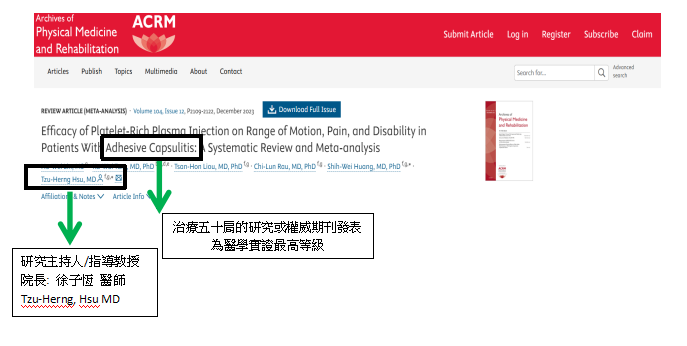

國際權威復建醫學期刊發表

專門治療五十肩的徐子恆院長,過去統整上千位患者案例,發表最高等級論文 於「美國復健醫學會」收錄於 「美國國家圖書館」。